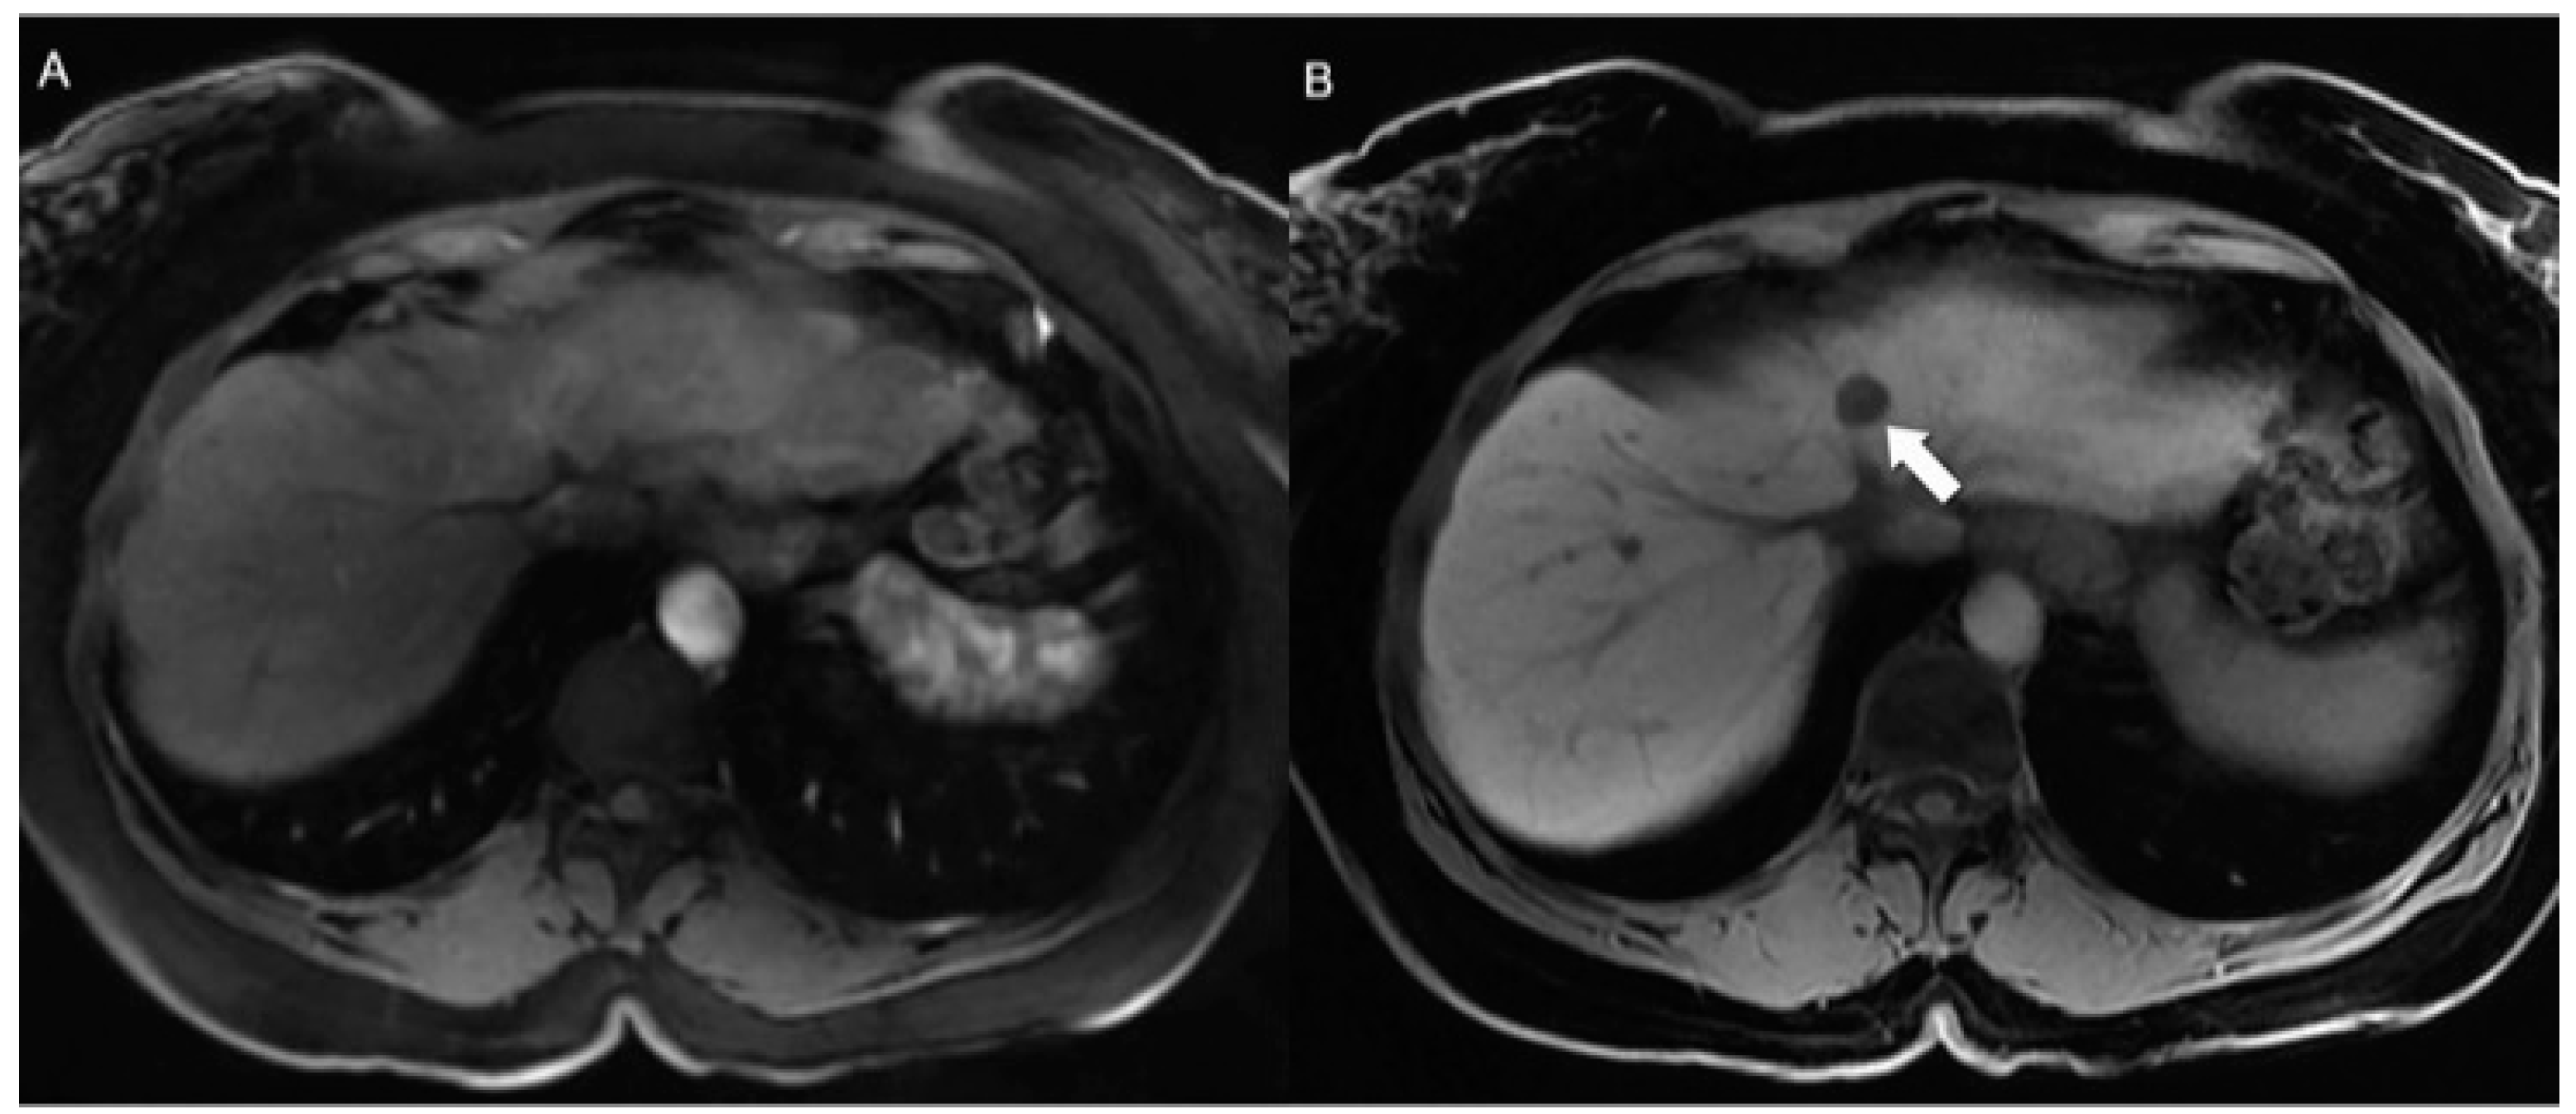

- Dromain, C.; de Baere, T.; Lumbroso, J.; Caillet, H.; Laplanche, A.; Boige, V.; Ducreux, M.; Duvillard, P.; Elias, D.; Schlumberger, M.; et al. Detection of Liver Metastases From Endocrine Tumors: A Prospective Comparison of Somatostatin Receptor Scintigraphy, Computed Tomography, and Magnetic Resonance Imaging. J. Clin. Oncol. 2005, 23, 70–78. [Google Scholar] [CrossRef]

- Tirumani, S.H.; Jagannathan, J.P.; Braschi-Amirfarzan, M.; Qin, L.; Balthazar, P.; Ramaiya, N.H.; Shinagare, A.B. Value of Hepatocellular Phase Imaging after Intravenous Gadoxetate Disodium for Assessing Hepatic Metastases from Gastroenteropancreatic Neuroendocrine Tumors: Comparison with Other MRI Pulse Sequences and with Extracellular Agent. Abdom. Radiol. 2018, 43, 2329–2339. [Google Scholar] [CrossRef] [PubMed]

- d’Assignies, G.; Fina, P.; Bruno, O.; Vullierme, M.-P.; Tubach, F.; Paradis, V.; Sauvanet, A.; Ruszniewski, P.; Vilgrain, V. High Sensitivity of Diffusion-Weighted MR Imaging for the Detection of Liver Metastases from Neuroendocrine Tumors: Comparison with T2-Weighted and Dynamic Gadolinium-enhanced MR Imaging. Radiology 2013, 268, 390–399. [Google Scholar] [CrossRef]